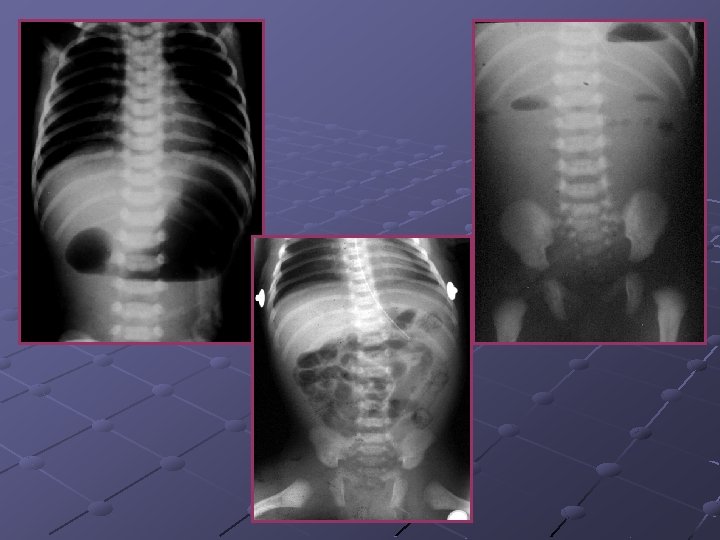

CAS N° 2 Absence d’émission du méconium Ballonnement depuis J 0 Bilan radiologique de J 2

Atrésie du grêle Interruption de la continuité intestinale Siège: duodénum (50%), jéjunum (35%) et iléon (15%) Facteurs fav évoqués: RCIU, consng. Infection maternelle, prise de cocaïne chez la femme enceinte… Prévalence: 0, 4 -2, 3 pour 10 000 Nces Théorie acceptée de nos jours: ischémie intestinale intra-utérine avec nécrose et résorption du segment concerné -thromboembolie -hypoxie fœtale -volvulus I-U -hernie interne -invagination intestinale aiguë